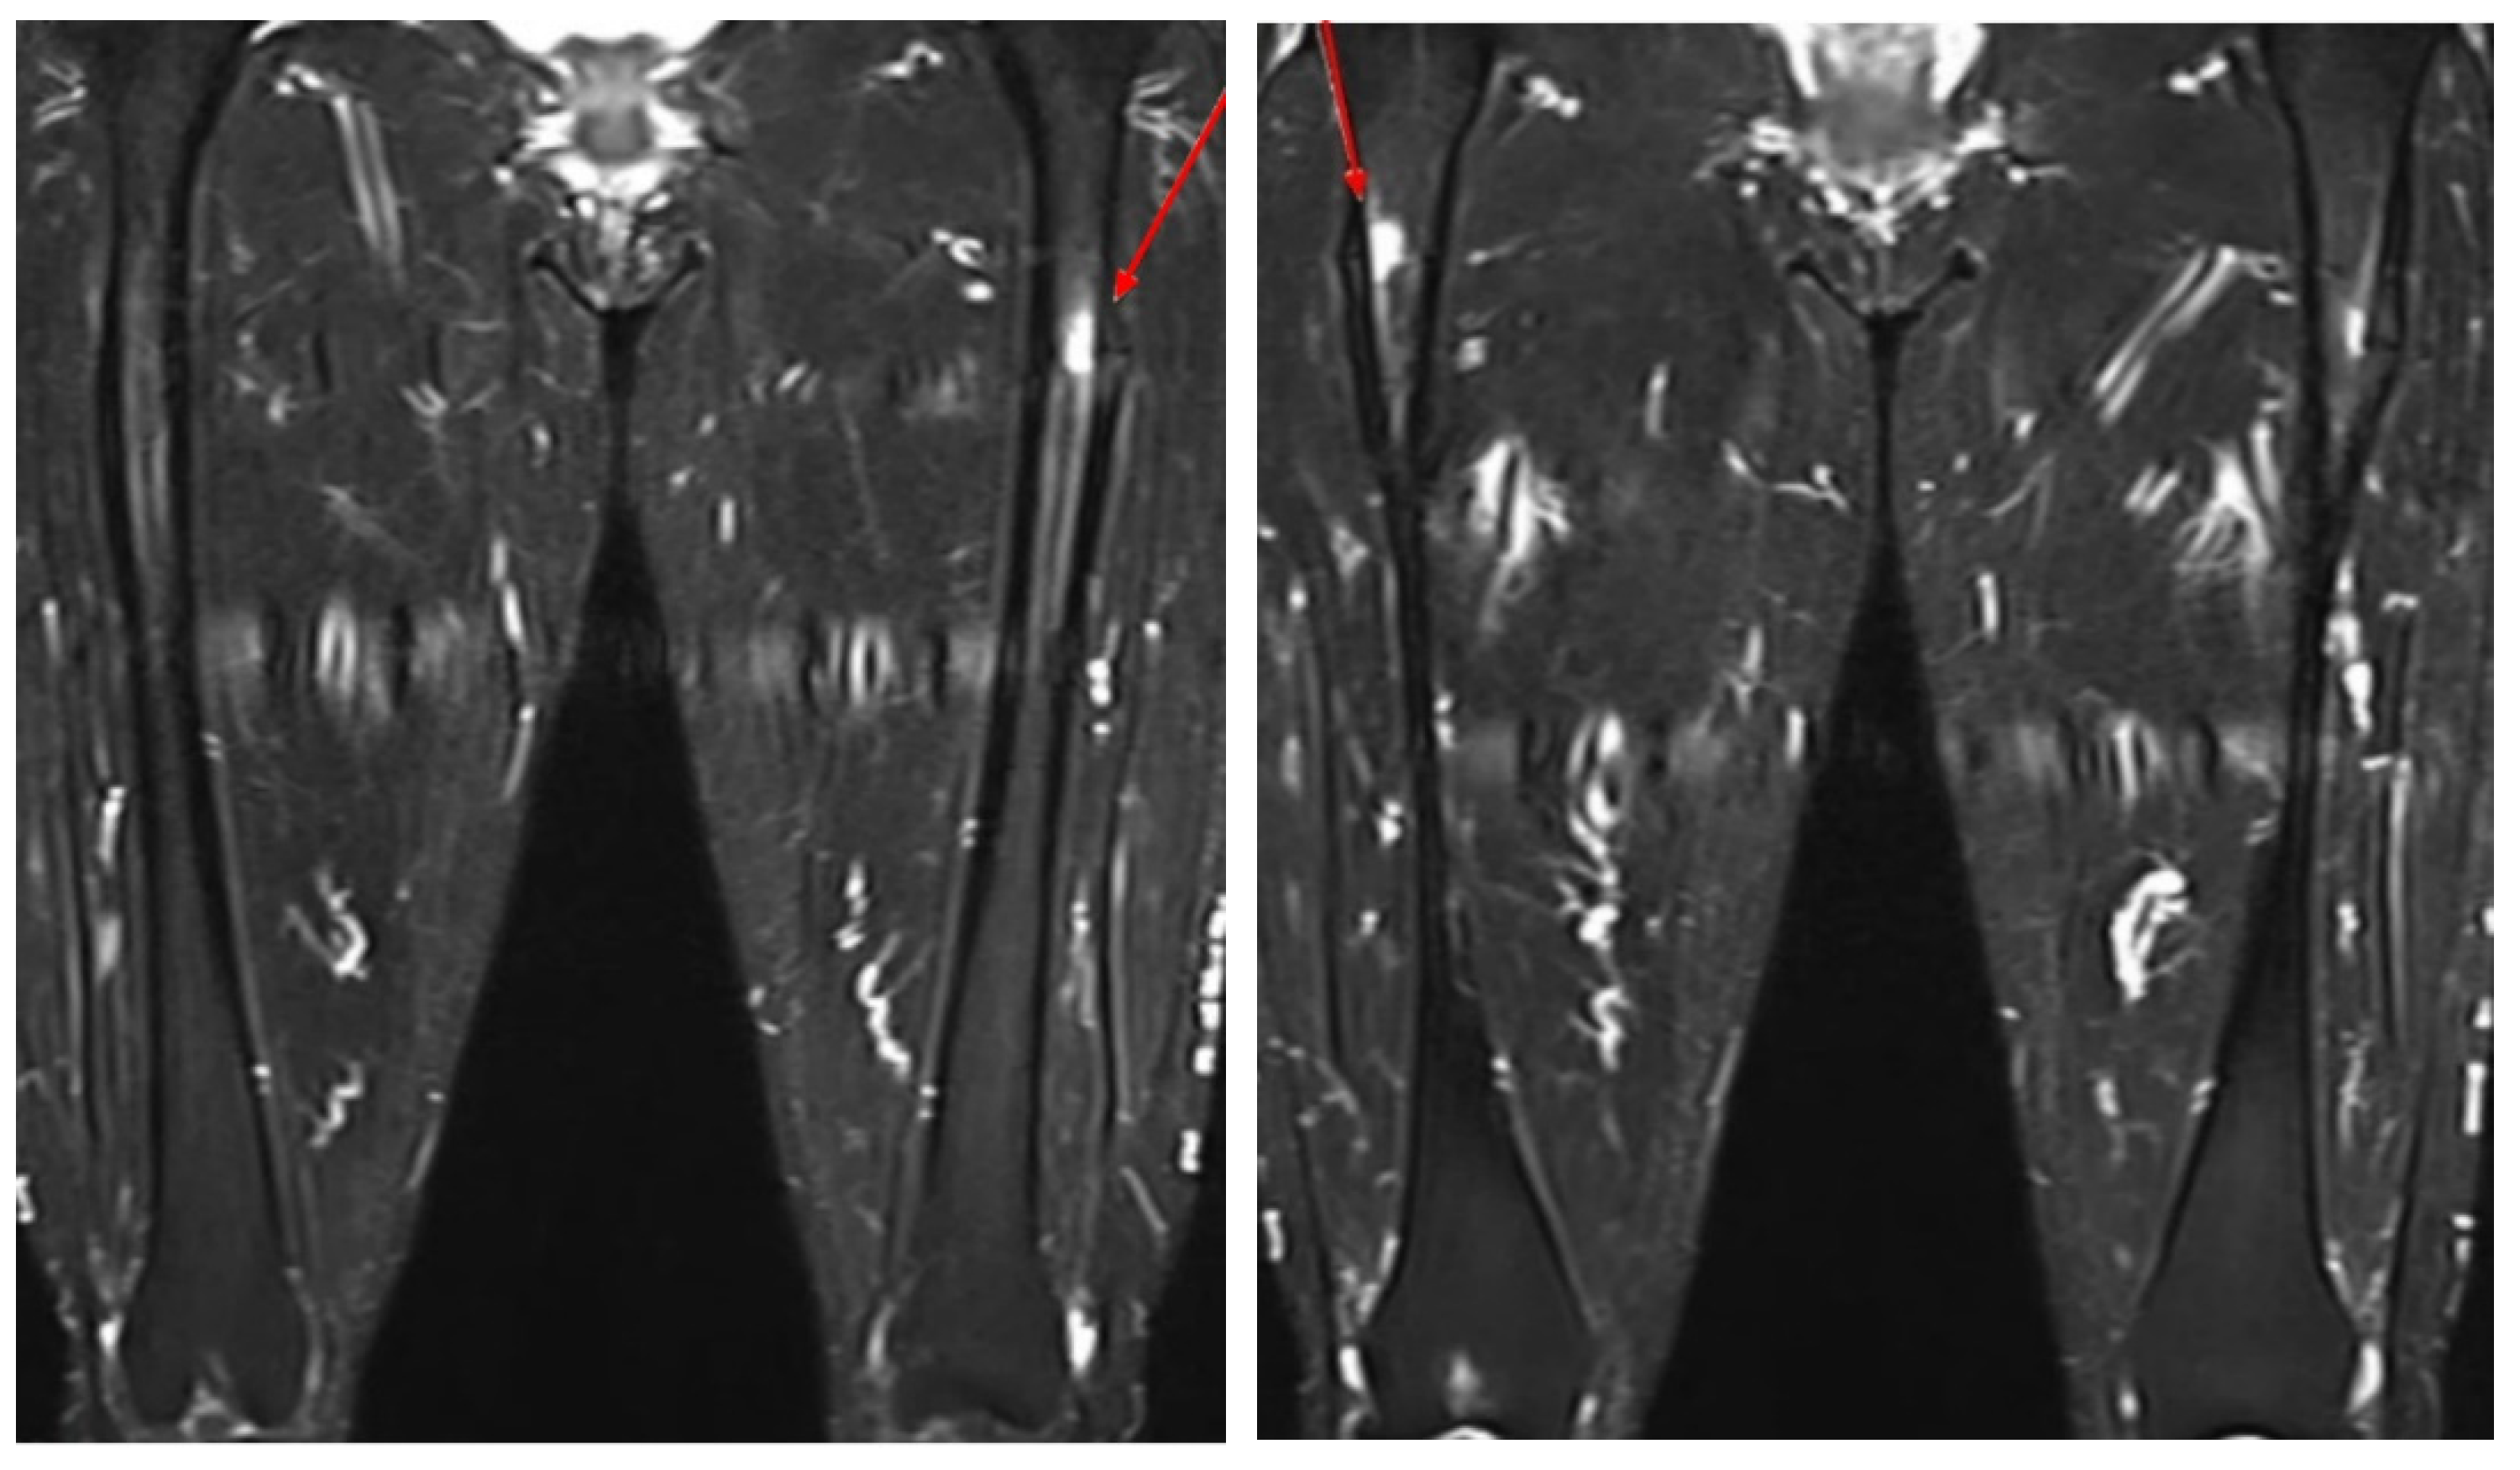

| 1 | Our case | F, 64 | O/O | Simultaneous | Ibandronate 150 mg monthly for 10 years | Prox/prox | PIM nailing/PIM nailing | Teriparatide | NA |

| 23 | Kosuke Hamahashi et al., 2020 [29] | F, 57 | O/O | Simultaneous | Zoledronic acid for 10 years | Prox/prox | IM nailing/PIM nailing | NA | 24 months/ 15 months |

| 24 | F, 57 | X/X | Sequential (3 years) | Alendronate for more than 10 years | Prox/prox | IM nailing/IM nailing | NA | 25 months/ 58 months | |